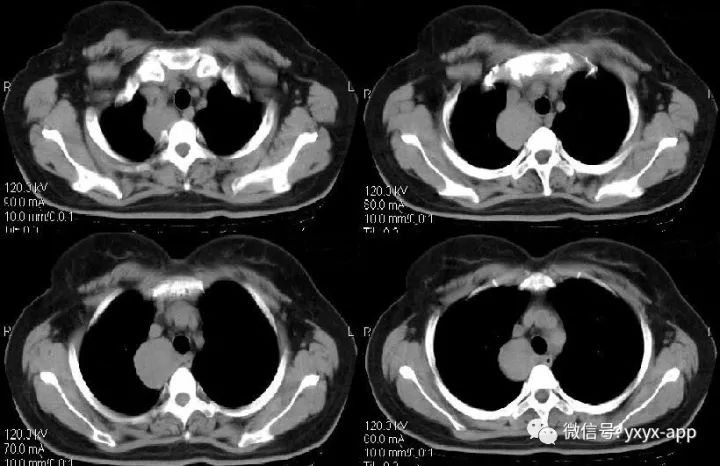

CT值在50-60hu之间

肚肚丫头:右上后纵隔、气管右旁、脊柱前方可见类圆形软组织密度影,与气管及食管均关系,增强后无明显强化,考虑囊肿,起源待定。

诊断:1.支气管囊肿;2.食管囊肿。鉴别诊断:神经源性肿瘤

【病理结果】支气管囊肿

CT表现:纵隔旁支气管囊肿其典型形态为圆形、类圆形、水滴形、长条形,偶为分叶状,边缘均清楚锐利,内部密度多较均匀。肺内型表现为单发的气囊肿、液囊肿、液-气囊肿或多发囊肿,边界清楚,囊壁薄而均匀,可合并肺发育不良、肺隔离症、肺气肿及胸廓塌陷等其他肺内畸形。CT值差异较大,多为20~30HU,最高可达80HU,反映囊肿内容物的不同成分,囊肿不与支气管相通时形成含液囊肿,与支气管相通时囊液会全部或部分排出,形成含气囊肿或含气液囊肿。如有感染、出血或囊壁受到刺激可以使壁增厚、毛糙,囊液也可以变得更粘稠,或者分泌的黏液含有高蛋白成分、钙乳样物质等,均可导致囊肿内密度增高,从而CT表现为软组织密度、实性肿块。CT增强扫描有助于判断囊壁及囊腔内容物的强化程度,提示诊断。支气管囊肿的强化特征为囊内容物无强化,囊壁可强化,是由于囊壁含有平滑肌成分,如合并感染、肉芽组织增生,囊壁可增厚、强化。